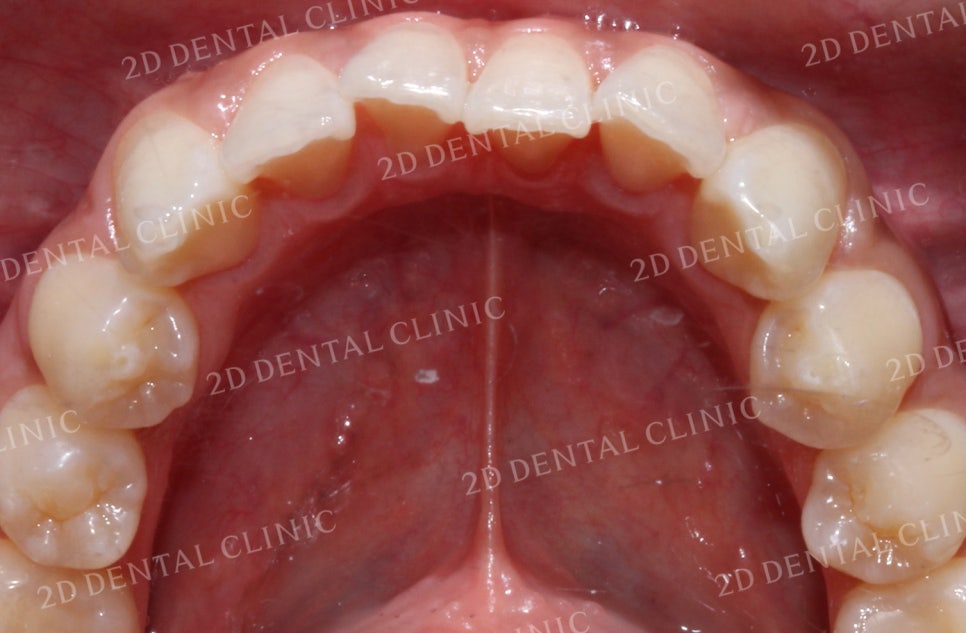

상악의 설측면 사진입니다.

상악의 경우 앞니와 송곳니가

미세하게 총생이 있어

전치부의 치아들이 전반적으로

삐뚤어진 느낌입니다.